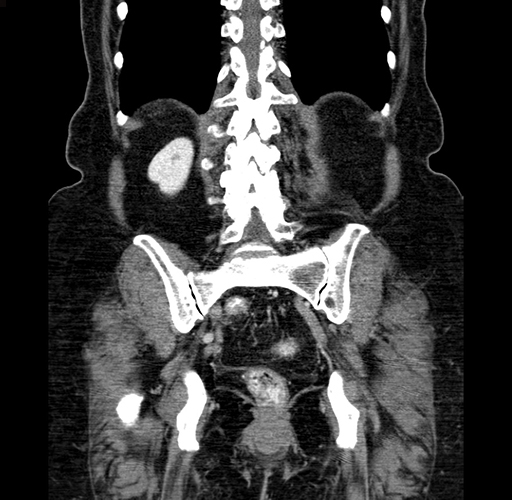

Pre-Chemo: Coronal Venous

Coronal Venous